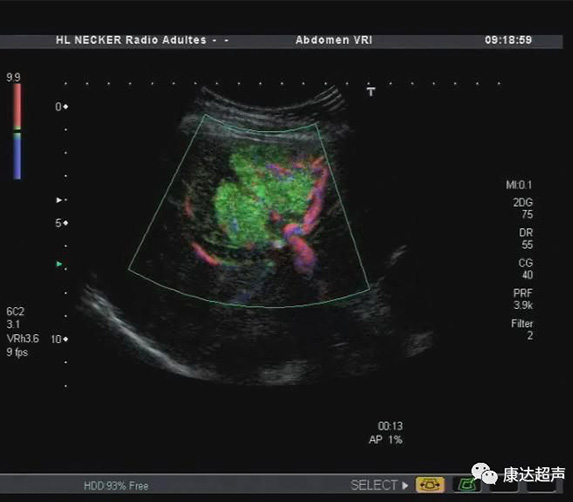

(VRI) VRI Technology

Using ultra-low mechanical index imaging technology. Both vascular blood flow and contrast perfusion information can be displayed simultaneously. The perfusion of the contrast agent is simultaneously displayed and differentiated in three different colors, the contrast agent perfusion of the larger blood vessels is directionalally displayed with the red/blue color, and the perfusion of the microvessels is displayed with high resolution in green color. The display of the contrast agent Wash in/Wash out achieves better results, and the direction of the blood vessels around the tumor can be observed directionally, which is beneficial to the judgment and analysis of tumor neovascularization. Simultaneous display of two-dimensional tissue imaging and contrast agent perfusion is extremely beneficial for the observation of small lesions and avoiding missed diagnosis of small lesions.